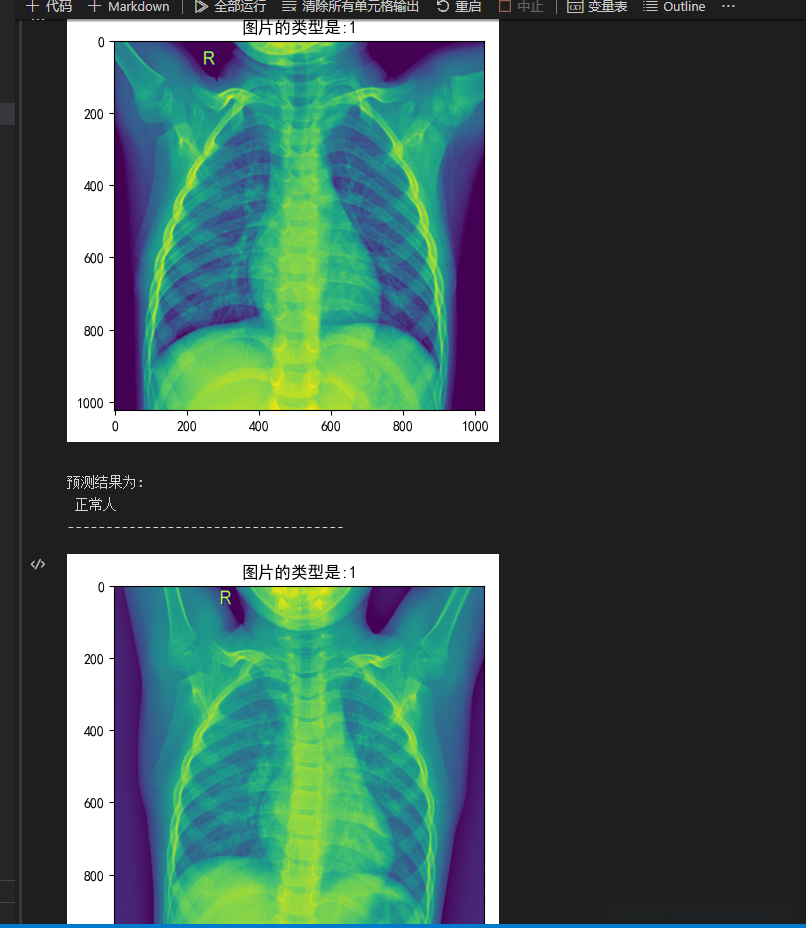

这段代码基于提供的验证数据集 val_image 和对应的标签 val_label 对模型进行预测运算,并将预测结果进行可视化呈现。

具体解释如下:

包含了分类标签的列表 label_list = ['新冠肺炎患者', '正常人', '病毒性肺炎患者'] 用于将预测结果归类到相应的类别中。

2. 外层循环 for j in range(len(val_image)): 遍历验证数据集。

内部循环 for batch_id, data in enumerate(eval_reader()): 逐批处理验证数据

调用 exe.run 函数来执行测试程序,并输入验证数据 data 以获取预测结果 results

5. 将预测结果转换为列表形式并保存在 results_list 中。

6. 遍历 results_list,将预测结果可视化展示:

通过调用plt.imread函数获取验证图像数据,并将其赋值给变量名val_image[i]

为当前图像设置标题,并将其内容指定为对应的真实标签值

通过调用plt.imshow函数显示图像内容

利用上述方法呈现待分类图像

借助计算库中的方法确定预测结果索引值

将预测结果信息存储于变量名中完成整个操作流程

输出预测结果信息

7. 如果 i == 5,即查看了 5 张图片后,跳出内层循环。

两个嵌套的break语句各自负责跳转至外部循环和内部循环,并且仅输出单一批次的数据

该代码片段的功能是用来利用已训练好的模型对验证数据集执行预测操作,并通过可视化手段展示预测结果。

label_list = ['新冠肺炎患者','正常人','病毒性肺炎患者']

结果展示: